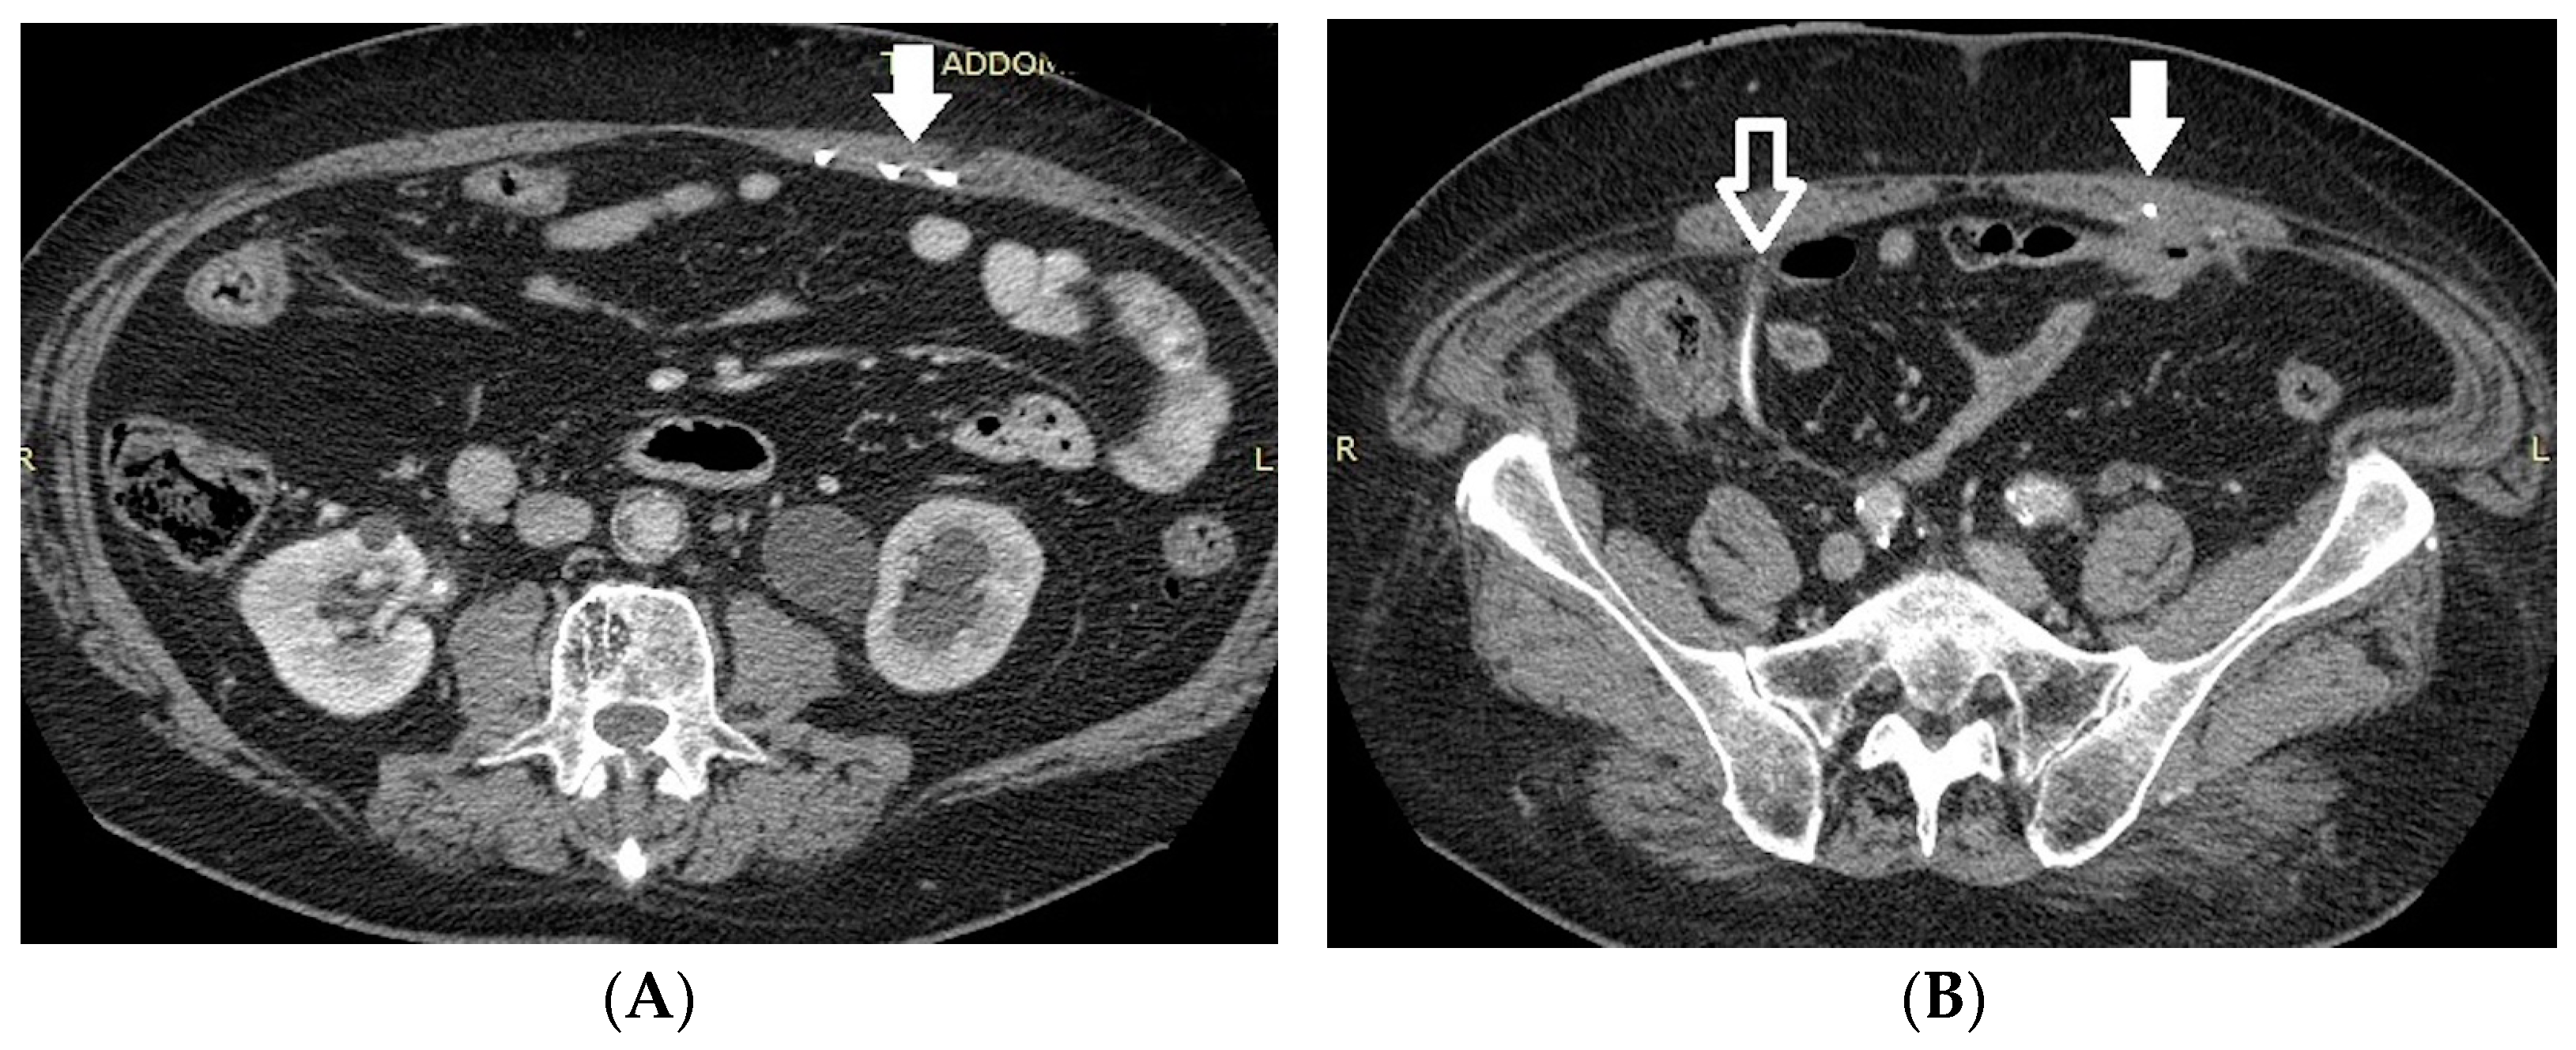

- Bleeding: The erosion of the stent into the arterial system is a rare and feared complication of ureteral stent placement, which can cause hematomas (Figure 10 and Figure 11), active bleeding, or pseudoaneurysm (Figure 12, Figure 13 and Figure 14). To avoid mortality from these complications, a high level of clinical suspicion is essential. Intermittent hematuria in a patient with a stent is typically the usual clinical scenario. However, massive hematuria and circulatory collapse can occur due to the manipulation of the ureteral stent [2,39].